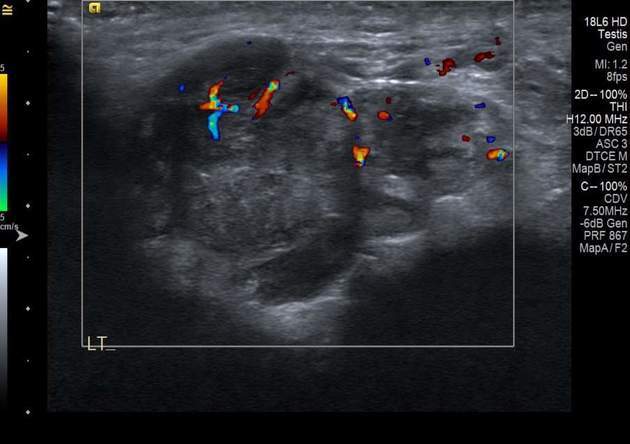

vascular paratesticular mass in a kiddo

think of?

Rhabdomyosarcoma

comes from epididymis or cord